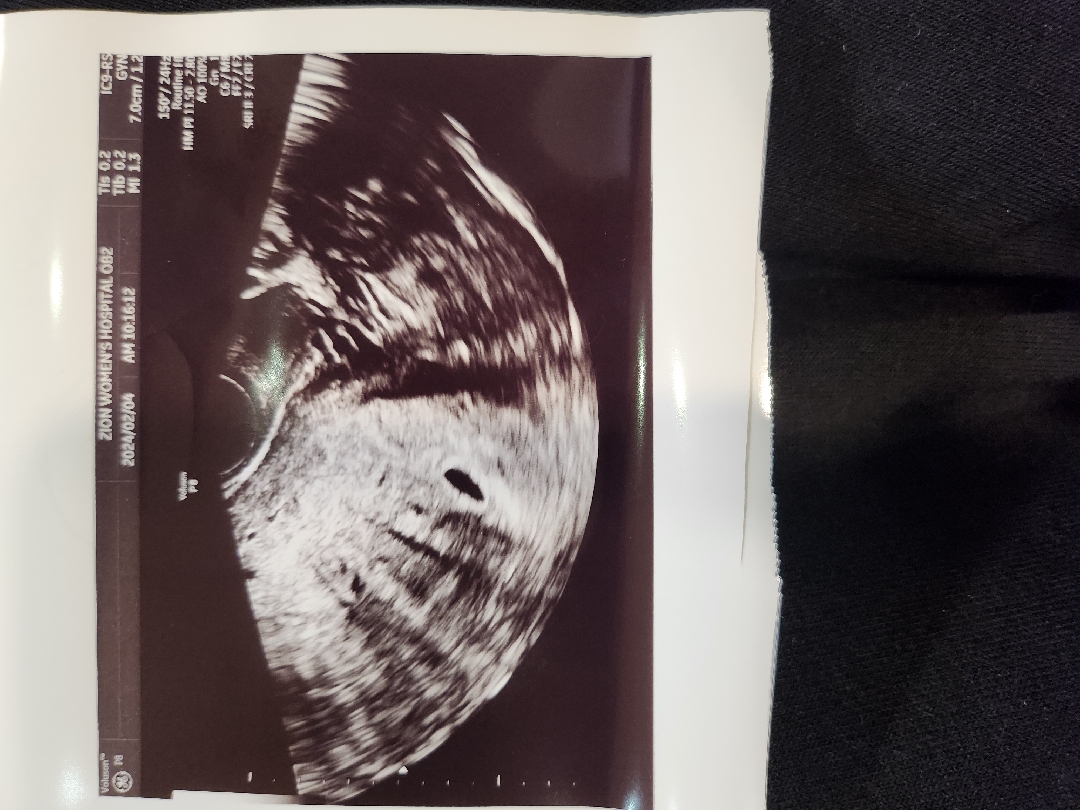

오늘 아기집 보고왔어요

막생으로는 5주3일차인데 의사쌤 말씀으로는 배란이 늦어진거 같다고 예정일 말씀해 주시는걸로. 계산해보니 4주5일차 정도됫네요~전 다음주면 심장소리도 들을 수 있겠다 하고간건데 2주뒤에 오래요ㅠ 자궁 선근종도 있고 나이도 있다보니..노산... 왠만하면 많이움직이지 말라고...... 선근종과 노산때문에 그런거겟죠?? 임신초기 여서가 아니구..??ㅠ ㅠ 이번 명절에 양가부모님께 임밍아웃 하려고햇는데.. 심장소리 들은 뒤 해야할지 고민이되요.. 지금도 입이 근질근질한데..